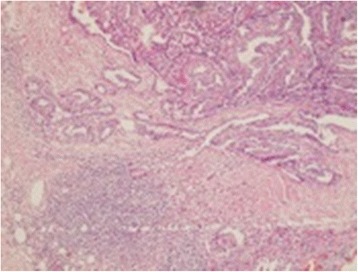

Postoperative pathology revealed recurrent papillary cancer at the right intraparotid mass, infiltration of 10 lymph nodes out of 16 lymph nodes of the left neck dissection and infiltration of one lymph node out of 11 lymph nodes in axilla by PTC (Fig. 3).

Fig. 3.

Histopathology of axillary lymph node showing metastatic papillary cancer